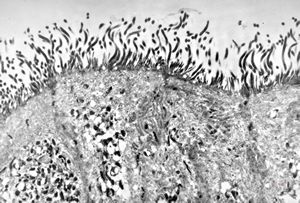

F,52y. | spirochetosis … colon (HE) … blue-stained brush border

F,52y. | spirochetosis … colon Warthin-Stary silver impregnation

F,52y. | spirochetosis - colon